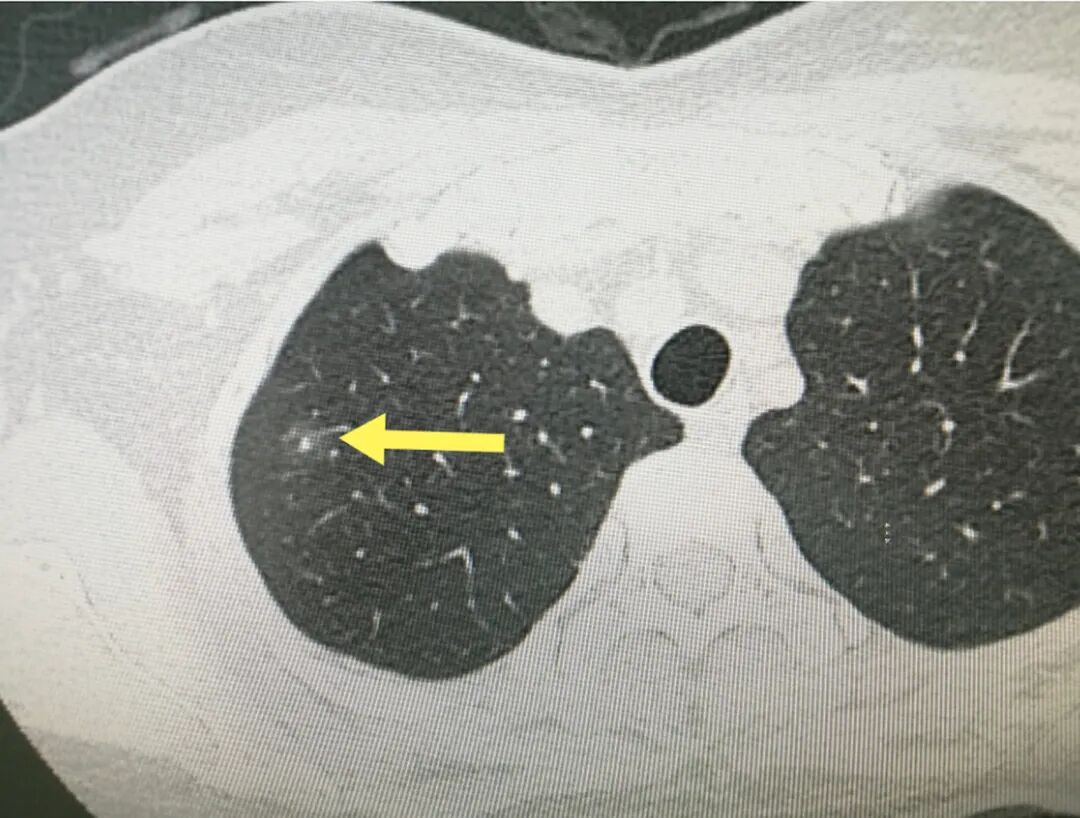

陈某,男,39岁,于2024年10月21日因“发现左肺磨玻璃结节2月”来我院就诊。患者体检时发现左肺存在一个11*12mm的磨玻璃结节。当时他无咳嗽、胸闷等任何不适,纳眠及二便均正常。

最终,患者遵医嘱,坚持上述综合治疗方案3个月后复查CT。令人欣喜的是,肺部磨玻璃结节已完全消失!为巩固疗效,后续再行短期治疗以善后。在整体的治疗中,出现了TTS治疗,而该项治疗在长期的临床应用中,证实对许多慢性病能达到标本兼治的目的,可大大缩短呼吸系统疾病的治疗疗程、减少并发症、改善肺功能、提高患者生存质量。